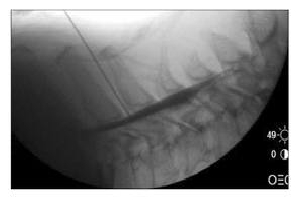

Injections for spine pain like cervical epidural steroid injections

- Interventional therapy: If a combination of physical and pharmacotherapy is unable to provide adequate pain relief then we should go for interventional (injection) pain management techniques such as cervical epidural and trigger point injections. These techniques are absolutely safe, effective and produce rapid recovery in all age groups provided they are performed by the experts (pain physicians).